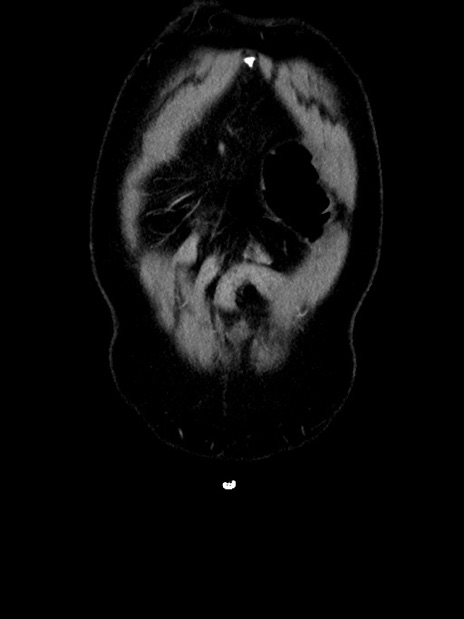

横断像

【症例】70歳代 男性

【主訴】腹部膨満、嘔吐

【現病歴】昨日より腹部膨満感出現。本日増悪し、仙痛出現。嘔吐あり、受診。

【既往歴】糖尿病、胆摘後

【身体所見】BP 149/80mmHg、HR 74/min、BT 35.9℃、腹部:膨満、軟、圧痛なし。腸雑音減弱あり。上腹部正中切開瘢痕あり。

【データ】WBC 13500、CRP 1.72